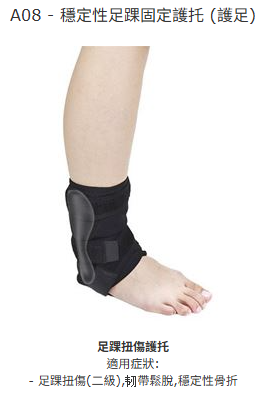

足踝扭傷護托

適用症狀:

- 嚴重足踝扭傷,韌帶撕裂,穩定性骨折

- 足踝扭傷(二級),韧帶鬆脫,穩定性骨折